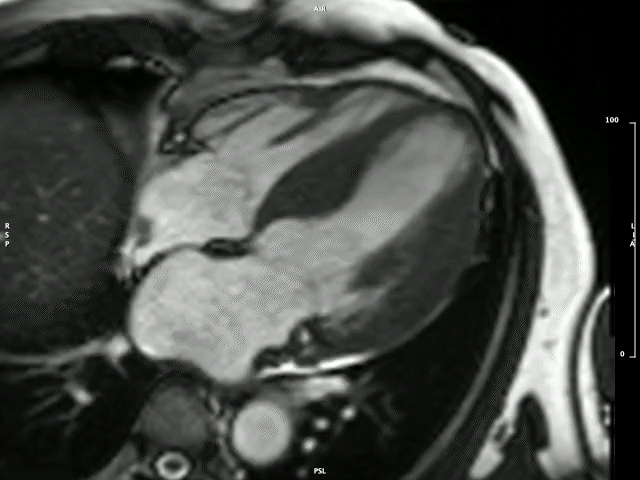

The Division is known locally and internationally as a centre of imaging excellence within both the clinical and research setting. The imaging expertise unit stretches across modalities, including 2D and 3D echocardiography, and state-of-the-art cardiovascular magnetic resonance (CMR) imaging that includes multiparametric mapping demonstrated below.

Left ventricular hypertrophy

Left ventricular hypertrophy in a patient with hypertrophy cardiomyopathy

Image by: Dr P-P Robbertse